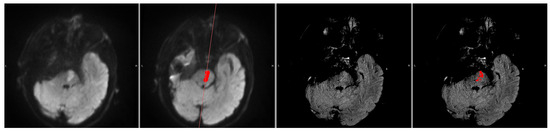

Figure 3. A sample with stroke across mirroring plane. From left to right: DWI (b1000), DWI (b1000) with segmentation (red area) and mirror plane (red line), FLAIR, and FLAIR with segmentation (red area). The ischemic stroke is located in such a way that the contralateral information comes from the stroke itself, making the automatic FLAIR segmentation unreliable.

3.2. DWI/FLAIR Mismatch Agreement

We ran the automated DWI segmentation as well as our FLAIR segmentation method on the Wake-up dataset. Out of the 51 cases, 4 cases were excluded due to the automatic DWI segmentation missing the stroke completely (Figure 2). A quantitative comparison between these patients with missed DWI segmentation and the rest of the cohort showed that the missed lesions all had subtle DWI lesions in regard to intensity. Furthermore, 1 case was excluded due to the stroke being located across the mirroring plane, with more than 20 % of the contralateral information being from the stroke itself (Figure 3).